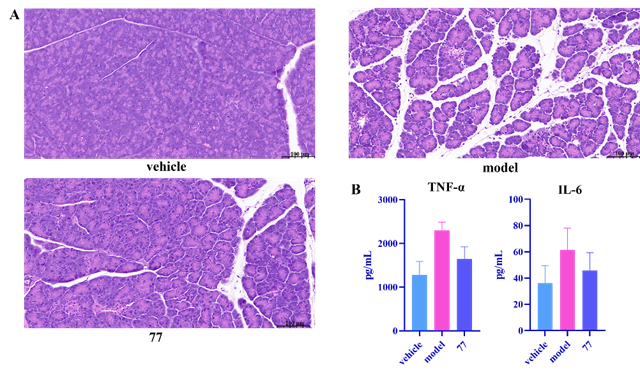

風濕性關節炎等慢性炎癥性疾病因高致殘率和現有藥物副作用大、療效不穩定等問題,而胰腺炎目前臨床沒有有效藥物,長期面臨治療困境。sEH在炎癥調控中至關重要,它代謝體內的有益的抗炎因子—環氧二十碳三烯酸,促使炎癥發展,成為抗炎藥物研發熱門靶點。不過,此前進入臨床II期試驗的sEH抑制劑,因藥代動力學缺陷或安全性問題折戟,目前沒有任何藥物被批準上市。這一現狀使得開發具有全新化學骨架的藥物變得尤為迫切,也極具重要意義。此前,我們設計了多種骨架的sEH抑制劑( European Journal of Medicinal Chemistry 2024, 266, 116113; European Journal of Medicinal Chemistry 2024, 280.; Journal of Medicinal Chemistry 2024, 67, 18412?18447; Journal of Medicinal Chemistry 2024, 67, 22168-22190.)。此次,我們基于“骨架躍遷”策略,從天然二苯乙烯衍生物出發,設計合成了九種新型骨架化合物,最終篩選出以“苯乙酰哌啶”為核心骨架的DJ-89。該藥物在多項實驗中表現出色:1)超強抑制活性:DJ-89對sEH的抑制活性(IC50 = 0.51 nM)比臨床候選藥EC5026(19 nM)和TPPU(44 nM)高數十倍。2)獨特抗炎機制:通過提升EETs水平并降低其代謝產物DHETs,DJ-89顯著抑制促炎因子(TNF-α、IL-1β)水平,同時增加抗炎因子IL-10水平,這一“雙效調節”機制具有創新性。3)體內顯著療效:在類風濕性關節炎大鼠模型中,DJ-89(10 mg/kg口服)有效減輕關節腫脹和骨侵蝕;在急性胰腺炎模型中,其抑制胰腺組織的炎癥細胞浸潤效果突出,同時血漿IL-6水平下降50%。4)優異的安全性:對hERG和CYP酶影響微弱,大幅降低臨床用藥風險。5)藥代動力學良好:口服生物利用度達8.3%,半衰期1.89小時,且主要富集于sEH表達量高的肝、腎部位,腦部暴露量低,預示其全身抗炎作用顯著且中樞副作用風險小。

圖3 在類風濕性關節炎模型中化合物77(DJ-89)的治療效果(左圖:大鼠關節腔切片,右圖:大鼠關節CT)